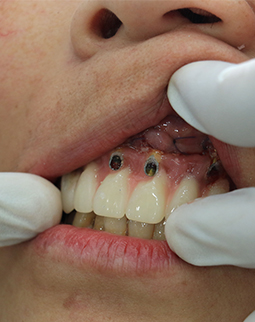

今天要做的第一件事,就是把半口的烤瓷牙冠全部拆掉,然后做了洗牙和局部上药消炎,等炎症控制好了以后,再说拔牙和种牙,医生跟我说,如果牙周炎症不做处理,口内的细菌太多拔牙后会出现感染,洁牙的过程很舒服,洁牙师和助理搭配,洗的很细心。身边不少朋友都担心洁牙会让牙齿变松,我到今天才明白,牙结石是造成我牙周炎症的主要原因,烤瓷牙是导致我根尖周炎的罪魁祸首,哎……强烈建议大家日常的口腔保健,1年两次洁牙还是要做起来的,积极的预防比后期的治疗更重要!洁牙完牙齿会更干净,口气也会清新不少。

在香港找了很多的口腔诊所,都说我的牙齿“病入膏肓”,要治疗的话只能全部拔掉种植,香港的消费实在很贵,所以我决定到深圳看看。好在遇到了深圳口碑比较好的口腔医院,他们帮我拆除了烤瓷牙冠,经过系列严苛检查,很耐心的跟我沟通牙齿问题,牙周炎症、蛀牙、牙髓炎等问题让我的牙齿已走到了末路,这被烤瓷牙吞噬的健康与口福,只能通过拔牙再种牙的方式来解决了。